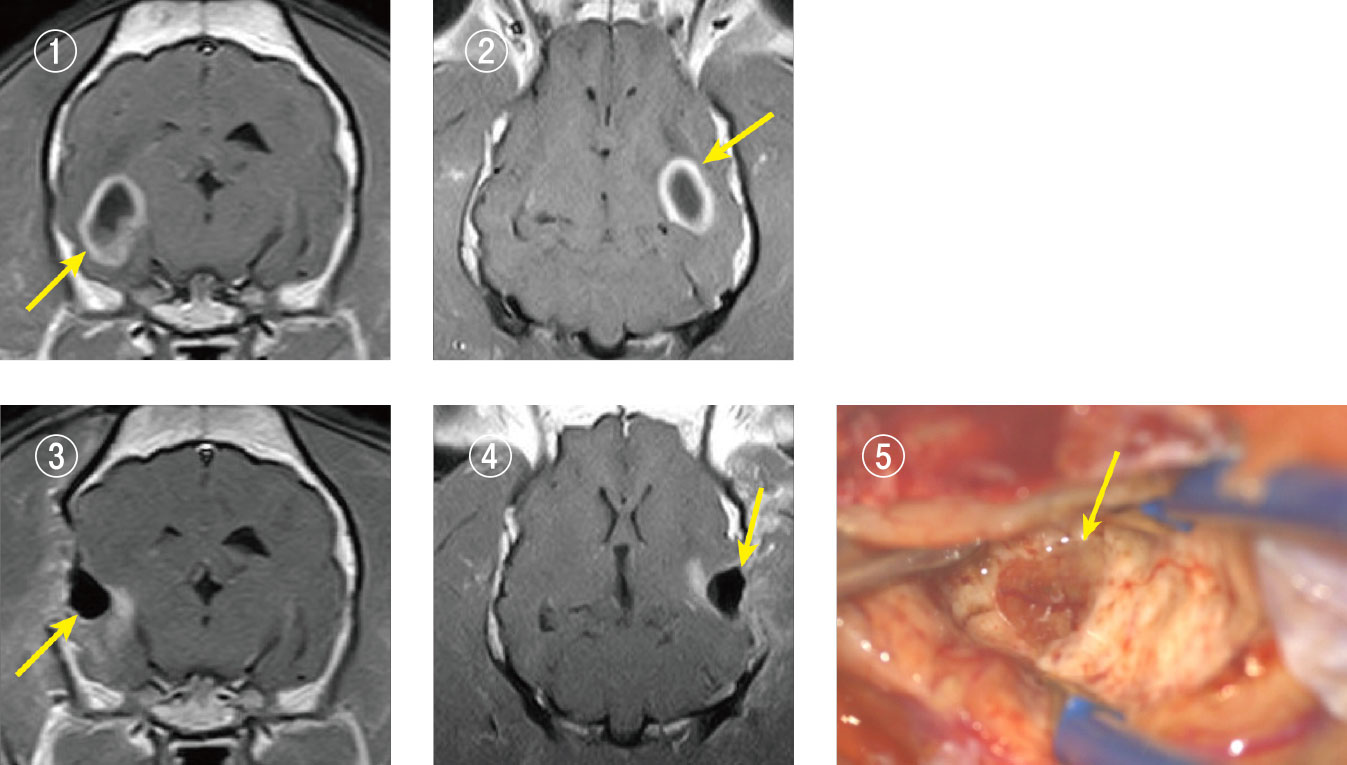

退形成性希突起膠細胞腫(悪性グリオーマ)

12歳のフレンチブルドックが発作で来院し、MRI検査で左の側頭葉内にリング状に造影される腫瘍が発見されました。脳の深い場所に腫瘍があり、正常な脳との区別が困難なことがあるため事前に染色液で腫瘍を黄色に染めておき、脳を切開して腫瘍に到達し可能な限り除去しました。病理検査では、退形成性希突起膠細胞腫と診断され、極めて悪性の脳腫瘍であることが判明したため、抗がん剤療法を行いました。その後しばらくして再発はみられましたが、ご家族との幸せな時間を過ごすことができました。

(写真説明)

写真① :手術前MRI画像(横断像)。脳内に白くリング状に造影された腫瘍が確認されました。

写真②: 手術前MRI画像(冠状断像)。脳内に白くリング状に造影された腫瘍が確認されました。

写真③: 手術後MRI画像(横断像)。腫瘍はほぼ消失しています。

写真④ :手術後MRI画像(冠状断像)。腫瘍はほぼ消失しています。

写真⑤ :手術用顕微鏡写真。脳を分け入っていくと淡く黄色に染まった腫瘍が確認されました。